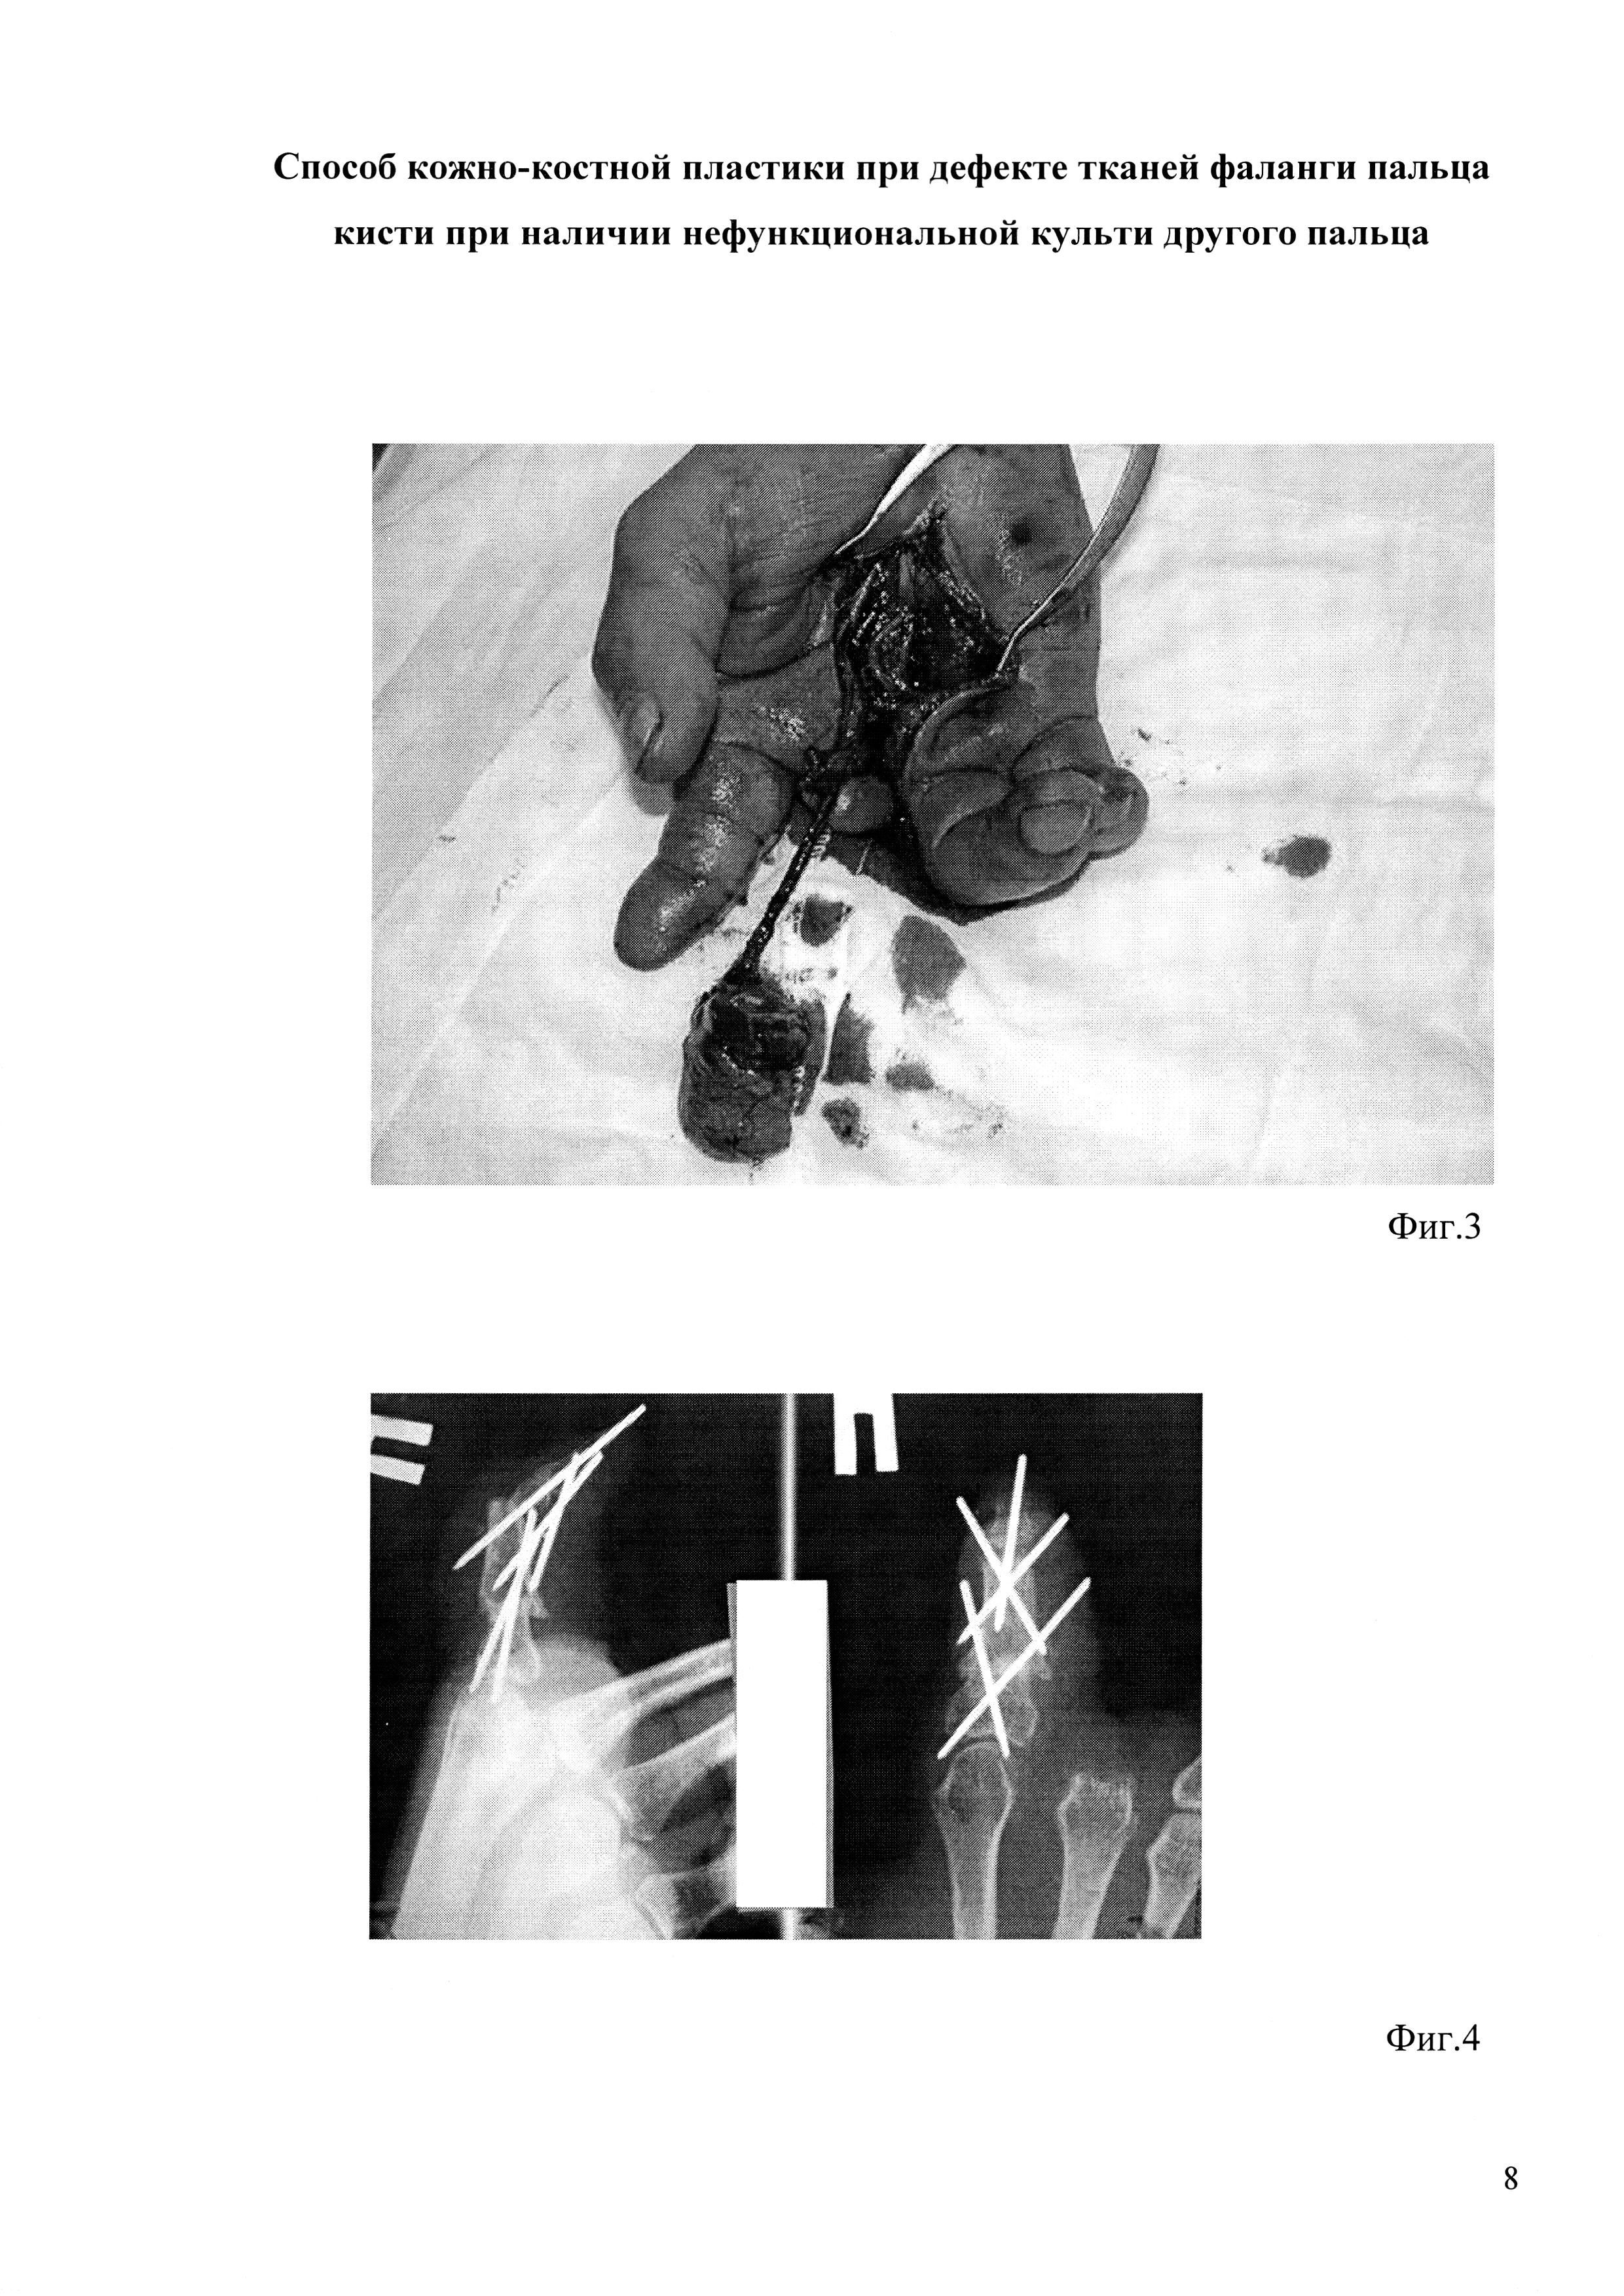

на фиг. 3 показан выделенный лоскут на удлиненной ножке;

[18]

на фиг. 4 - рентгенография после пересадки лоскута;

[19]

Произвели измерение размеров сочетанного дефекта и культи пальца, выделили (фиг. 2) и подняли кожно-костный лоскут (фиг. 3), пересекая при этом один сосудистый пучок и оба пальцевых нерва на уровне собственных пальцевых сосудов на границе лоскута. Пересекли поверхностную артериальную дугу на участках по сторонам от пальцевых артерий, идущих к культе, с сохранением дуги на участке между пальцевыми артериями. Лоскут переместили в реципиентную область и зафиксировали (фиг. 4). Произвели реиннервацию лоскута посредством эпипериневрального шва между пальцевыми нервами. Раны зажили первичным натяжением, без осложнений. Больной удовлетворен достигнутым результатом (фиг. 5).